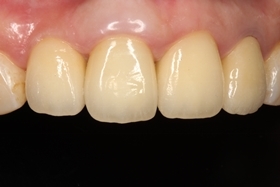

假牙完成後,植牙與自然牙,真假難辨;病患恢復自信的笑容。